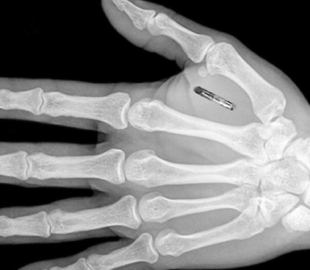

В Швеции был разработан микрочип, который имплантируют под кожу и загружают туда ковид-паспорт. Имплант, размером с рисовое зернышко, способен хранить не только данные о вакцинации, но и другие важные документы.

По словам руководителя компании Ханнеса Сджоблада, микрочип подшивают под кожу между большим и указательным пальцами, или немного выше запястья с помощью специального шприца. При желании его можно без проблем удалить в любой момент.